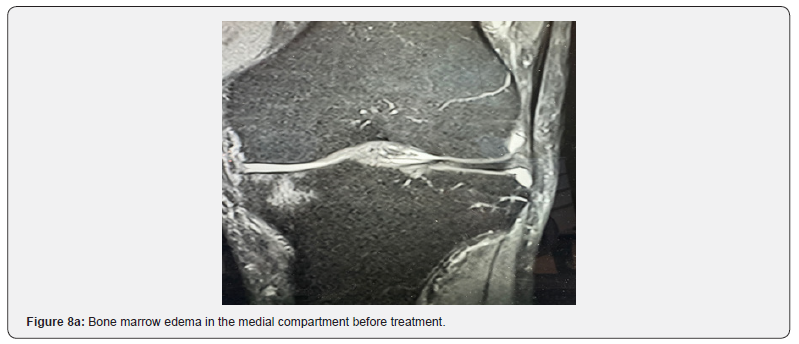

In all patients, OA symptoms improved after one single injection of 10 mL stem cells combined with their exosomes. There were no adverse effects related to the injection. No patients reported worse or equal symptoms at six months follow-up. Eight patients had slightly increased pain associated to knee swelling during the first three days after treatment which was treated using ice packs and a non-steroidal antiphlogistic drug (Paracetamol 500 mg). VAS significantly improved in all patients six months after the intervention. Also, KOOS values showed significant improvement after six months in all patients. All patients stated they are satisfied and also stated they should have undergone the procedure earlier. The results are presented in Figures 2-7. In 11 patient magnetic resonance imaging (MRI) scans showed successful treatment of bone marrow edema after 6 weeks despite full weight bearing. Figure 8 shows the MRI scan of a 79-years old male patient before and after the intervention.

In a systematic review the authors found that stem cells derived from peripheral blood can repair cartilage and are an important resource to treat cartilage injuries. Also, the role of exosomes has been highlighted repeatedly in recent past. Wu et al described that exosomes can rewire the cartilage microenvironment in patients with OA and pointed out their role for cartilage repair in future [30]. This was also mentioned by He et al who found that exosomes are able to reduce pain and cartilage defects in a rat model of OA. The role of exosomes on the reduction of proinflammatory cytokines was also emphasized by He et al. [31]. Also, in our patients we found pain reduction at very early stages (first follow-up after three days) that might be attributed to the shift from pro- to anti-inflammation. It was surprising, though, that also bone marrow edema disappeared as visualized on MRI per- and post-intervention.